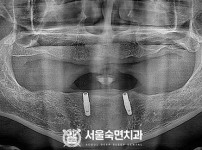

임플란트-전후사진1